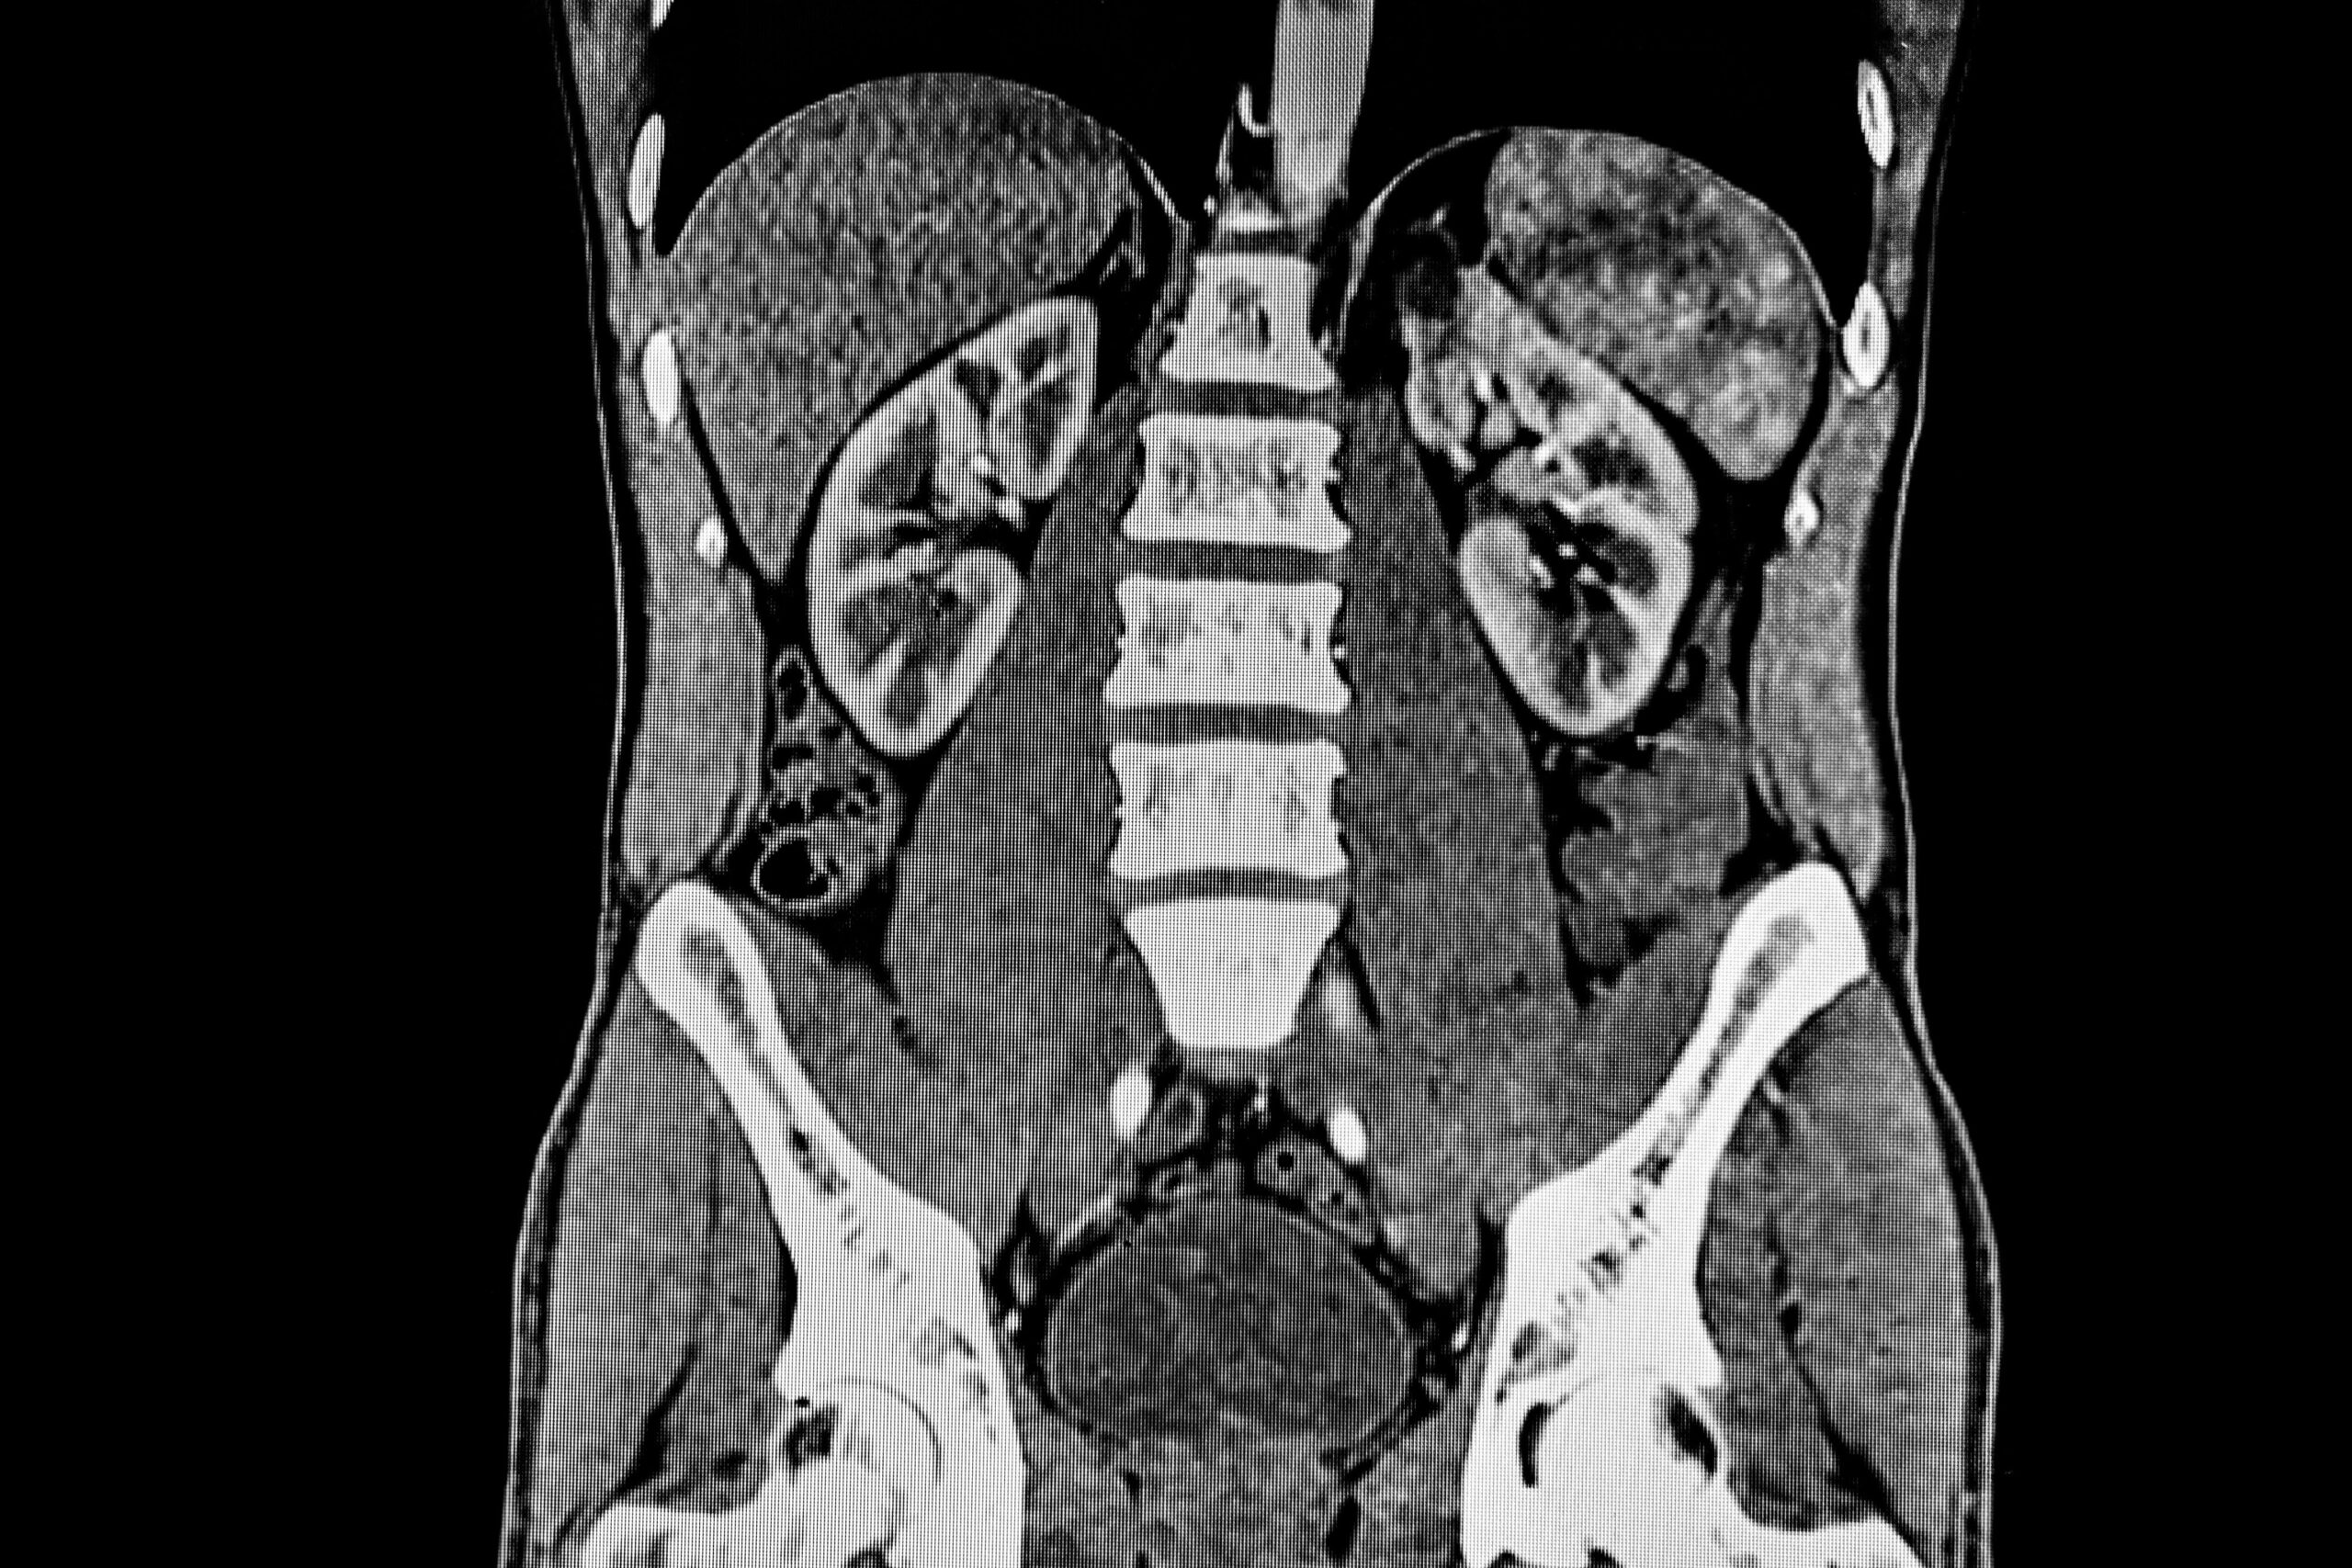

A pelvis with contrast refers to an imaging study, typically a CT (computed tomography) scan or MRI (magnetic resonance imaging), where a contrast agent—such as iodine-based dye for CT or gadolinium for MRI—is administered to enhance the visibility of structures within the pelvic region. Unlike a plain X-ray, this technique highlights not only the bony framework (hip bones, sacrum, and femur) but also soft tissues, blood vessels, and organs like the bladder, reproductive organs, and lower gastrointestinal tract. The contrast is usually introduced via intravenous injection, oral administration, or rectal enema, depending on the specific area of interest, and it works by altering the way X-rays or magnetic fields interact with tissues, making abnormalities like tumors, infections, or vascular issues stand out more clearly. This method provides a detailed, multi-dimensional view, allowing radiologists to detect conditions such as pelvic inflammatory disease, cancers, or abscesses that might be missed on a plain film. While highly effective, the use of contrast requires consideration of patient factors like kidney function or allergies, as the agents can occasionally cause side effects, and it’s typically reserved for cases where plain imaging is insufficient.

Pelvis with Contrast